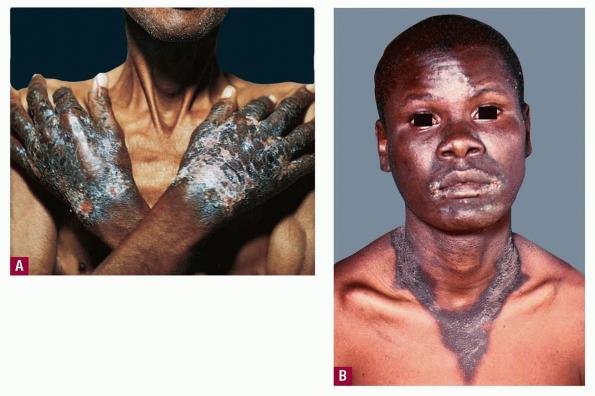

Three basic skin eruptions occur in pellagrins . The first is a photo-induced eruption that is intensely erythematous and subsequently exfoliates to yield a hyperpigmented residuum. The second eruption comprises painful erythematous erosions in genital and perineal areas possibly induced by pressure, heat, and trauma . The increased skin fragility may reflect aberrations in the collagen and elastic fiber content of the skin. Pellagrins may develop a seborrheic dermatitis-like rash involving the face, scalp, and neck. Oral manifestations include beefy, red, cracked lips and a fissured or smooth, red, sore tongue . Among the neurologic symptoms are dementia, psychosis, anxiety, defective memory, burning sensations, sudden attacks of falling, dizziness, and headaches. A cause of sudden death is central pontine myelinolysis .

. Psoriasiform epidermal hyperplasia with hyperkeratosis, parakeratosis, and a lymphocytic perivascular inflammatory cell infiltrate characterize initial lesions. Additional features include scattered necrotic keratinocytes, granular cell layer loss, and architectural disarray with dysmaturation of the epidermis. Depigmentation of the basal layer with accumulation of fat droplets is described, as is vacuolation of cells within the granular and spinous layers . Epidermal atrophy, hypermelanosis, vascular ectasia, and sebaceous atrophy characterize end-stage lesions . Seborrheic dermatitis-like lesions may show sebaceous gland hyperplasia with follicular dilation. Fragmentation, swelling, and thickening of elastic fibers, swelling of collagen fibers, and merging of elastic tissue with collagen have been described. A morphology indistinguishable from that of necrolytic migratory erythema and acrodermatitis enteropathica has been reported, comprising intracellular edema with vacuolar change of the upper stratum malpighii and keratinocyte necrosis, sometimes accompanied by neutrophilic infiltration of the upper spinous layers, subcorneal pustulation localized to or in isolation from these areas, and folliculitis .